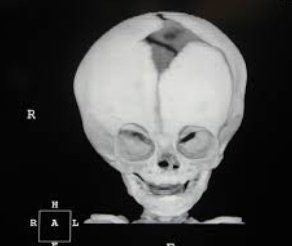

1- تشوهات العظام

تؤدي الثلاسيميا الى تمدد نخاع العظم مما يجعل العظام تمدد عرضاً، وقد يؤدي هذا الى حدوث شذوذ في بنية العظام خاصة عظام الوجه والجمجمة، كما يؤدي التمدد الى ترقق العظام وهشاشتها مما يزيد فرص كسور العظام